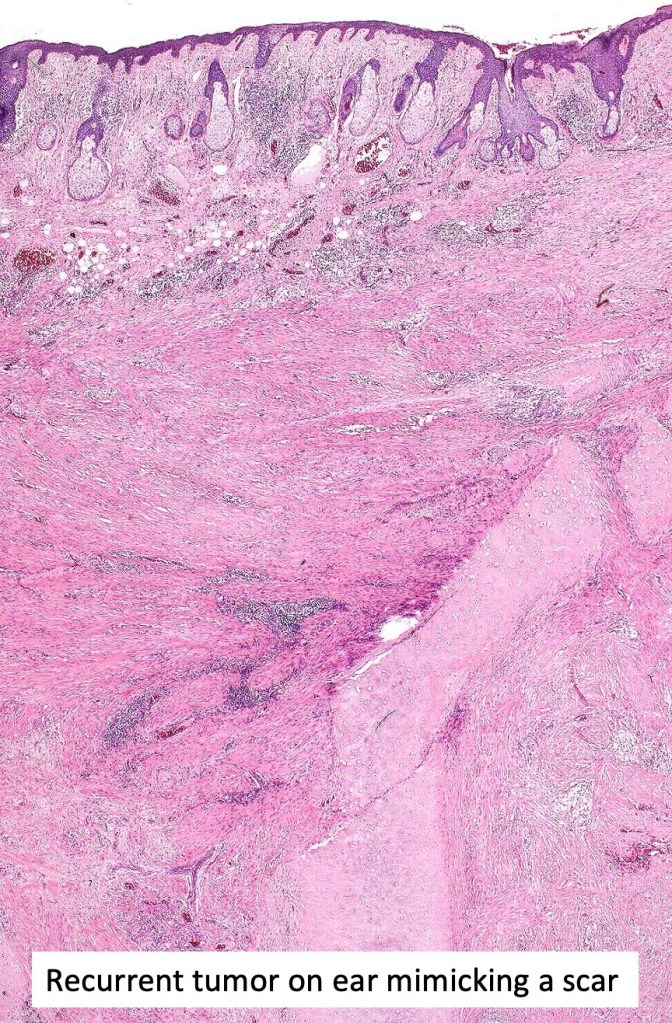

. Pure desmoplastic variant frequently recurs & can be deeply invasive

Pure forms require a high index of suspicion and frequently IHC is required if a junctional component is not evident. Desmoplastic melanoma can be mistaken for a scar (never report on a scar if the clinical history doesn’t detail what the original lesion was!!) Other tumors with which it can be confused include desmoplastic spindle cell squamous carcinoma, neurofibroma, dermatofibroma, nodular fasciitis, fibromatosis, spindle cell atypical fibroxanthoma, sarcoma particularly neurofibrosarcoma (especially if only a shave biopsy is submitted).